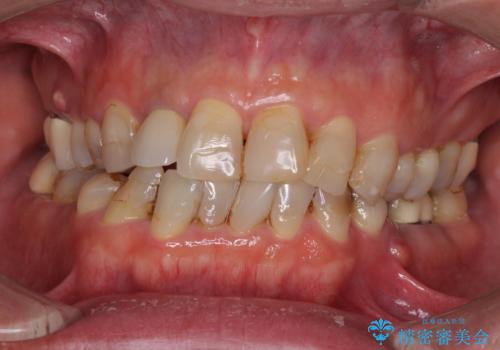

薄くて退縮しやすい前歯の歯肉 補綴治療前に歯肉移植で退縮しにくく

- 前歯のオールセラミック治療を検討しているとのことで来院された患者様です。

前歯は着色や虫歯治療の跡が目立っている状態で、オールセラミッククラウンによる審美治療を希望されていました。

歯肉が非常に菲薄であり、オールセラミッククラウンを装着後の近い将来歯肉退縮によりセラミックの境目が見えてくることが懸念されました。

まずは歯肉移植術により顕著に露出している歯根面を被覆して自然な歯肉ラインとし、同時に歯肉の厚みを増大させることで将来の歯肉退縮を予防することを提案しました。